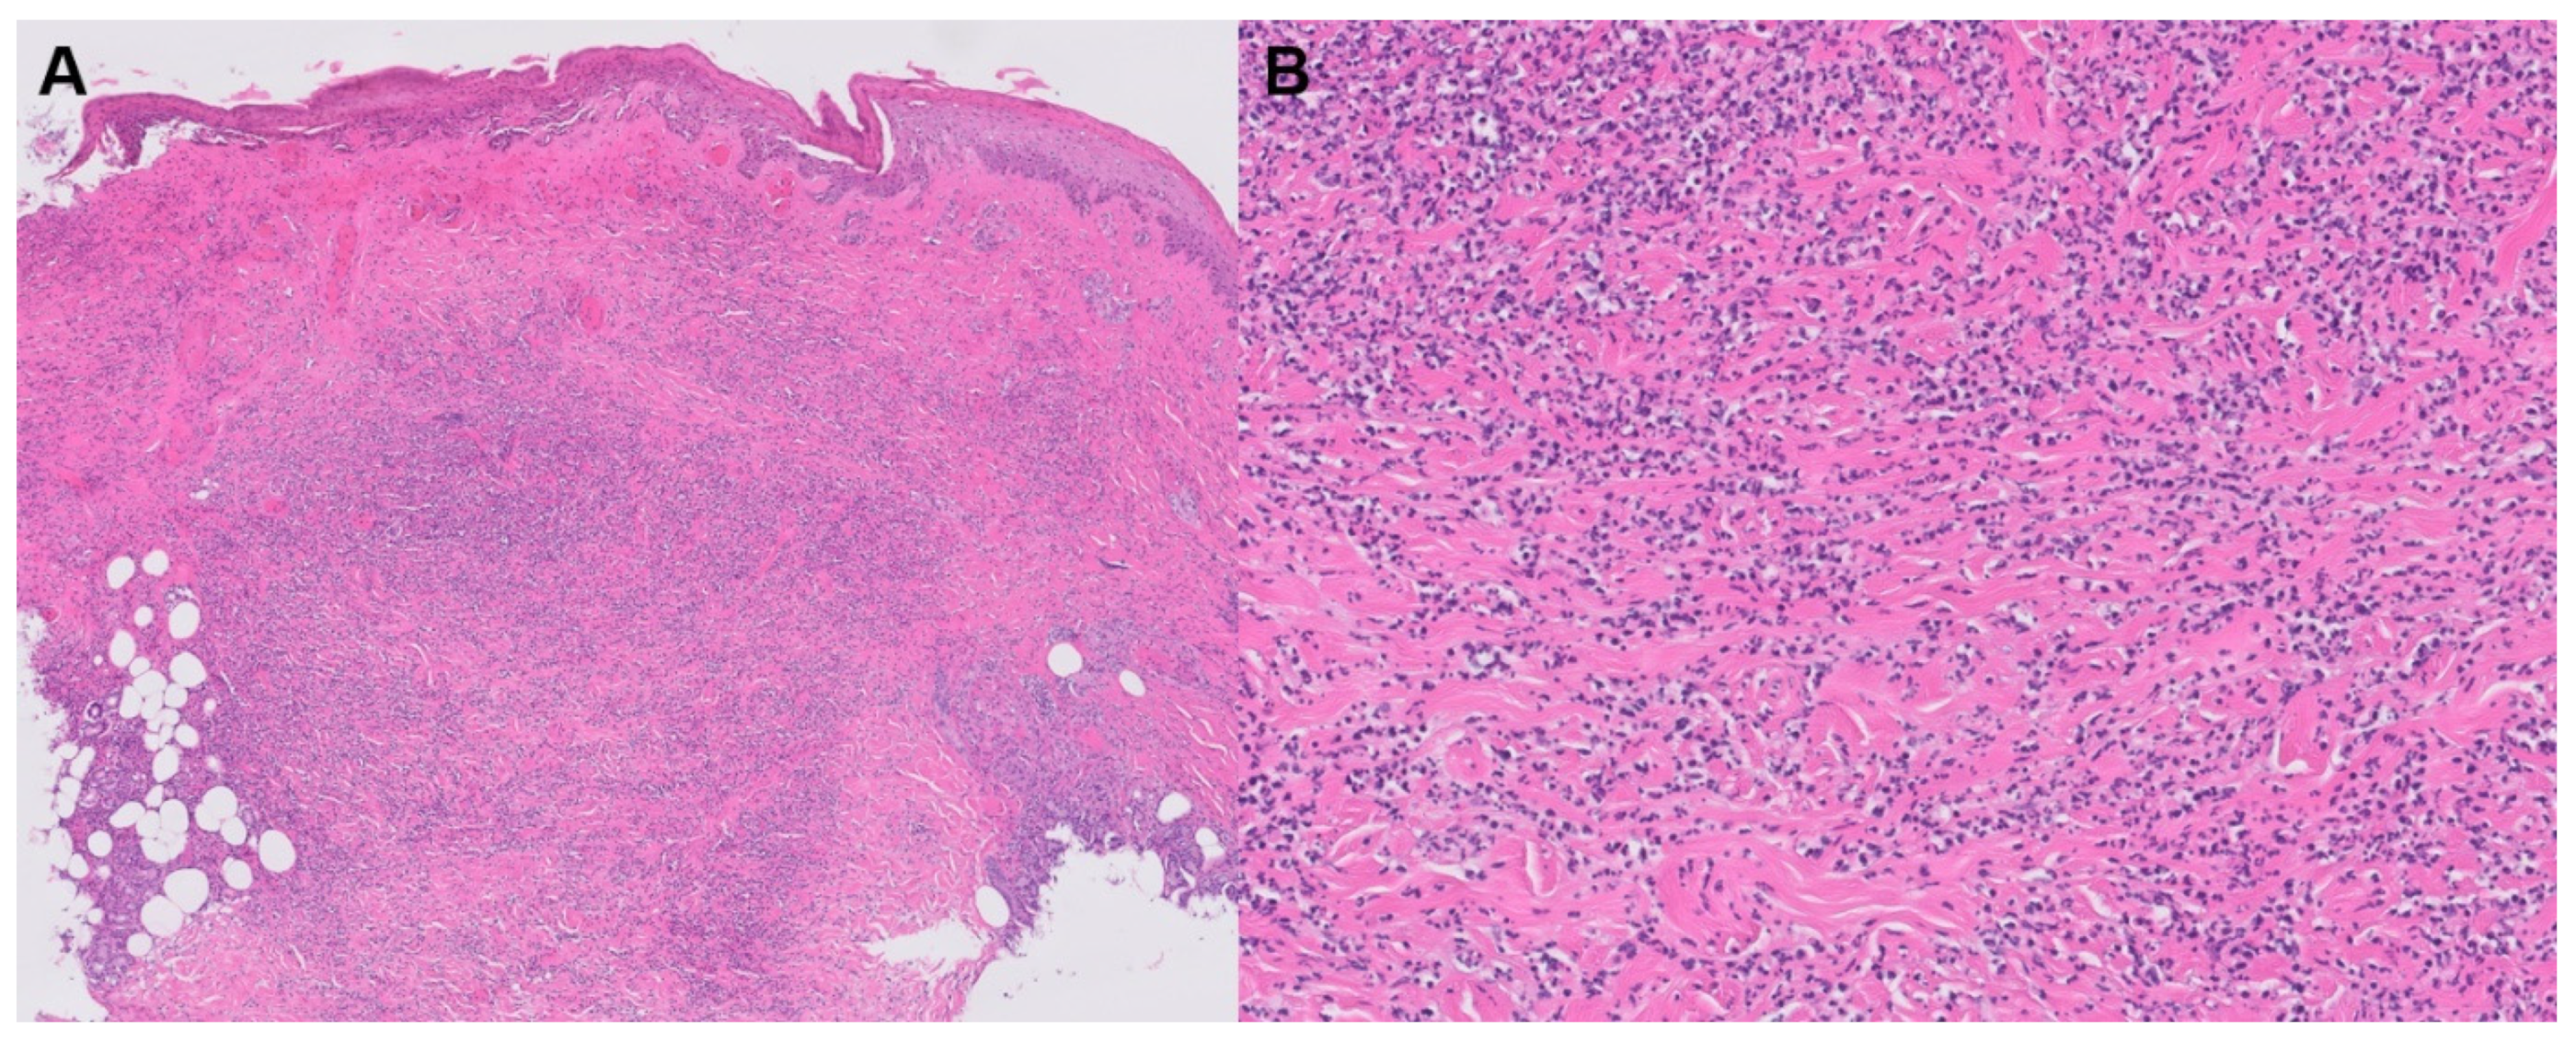

3.2.4. Palisaded Neutrophilic Granulomatous Dermatitis and Interstitial Granulomatous Dermatitis

| PNGD and IGD | -PNGD: symmetric smooth, umbilicated, or crusted papules, often on the elbows and extremities with skin to erythematous color -IGD: shared clinical features with PNGD, with locations favoring the lateral trunk and skin folds | -IGD: lympho-histiocytic infiltrate -PNGD: Greater neutrophil infiltrate | -PNGD, histologically: leukocytoclastic vasculitis, Sweet syndrome, neutrophilic urticaria | -Management of underlying condition -Noted clinical improvement with topical or oral corticosteroids, oral dapsone, and hydroxychloroquine |